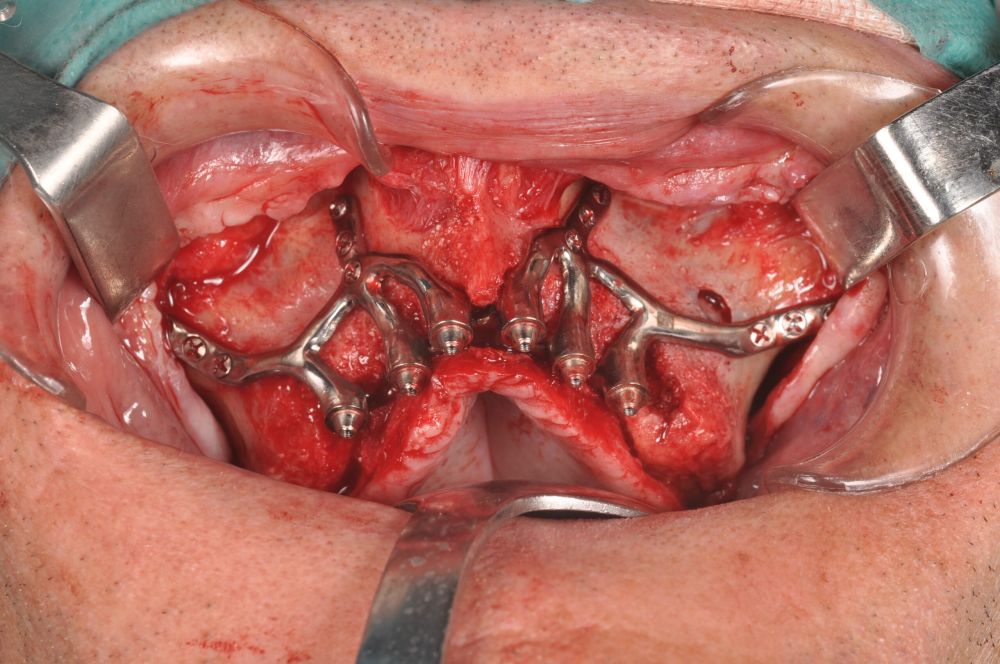

The surgical procedure was performed under general anaesthesia and nasotracheal intubation. A supracrestal incision and detachment of a maxillary flap of total thickness was made (Figures 9 and 10). The boundaries of the dissection were both infraorbital ridges, both laterally malar bodies and the anterior half of the hard palate caudally. In addition, a customized cutting guide was used so that the SI was completely in direct contact with the bone (Figure 11) and the mesh was fixed with the different 1.5 mm osteosynthesis screws in the nasal and zygomatic buttresses (KLS Martin, Freiburg, Germany) (Figure 12). The closure was performed with nonresorbable suture. Finally, the PMMA provisional rehabilitation was screwed for the immediate load, with a torque of 20 N on the implants (Figures 13-15).